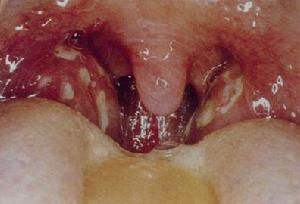

(2)心肌膜炎:以二尖瓣最常受累,主動脈瓣次之。心尖部出現Ⅱ至Ⅲ級吹風樣全收縮期雜音,有時音調高,如海鷗鳴,雜音向腑下及左背傳導,呼吸與體位對雜音無影響。此雜音提示二尖瓣關閉不全。約有半數心尖部可伴有Ⅱ至Ⅲ舒張中期雜音(carey-coolmbs),由於左室張舒張期快速充盈或二尖瓣口相對狹窄引起。一般在急性期於二尖瓣區聽到的雜音並不一定代表瓣膜已發生不可恢復的器質性損害。輕型心臟炎病兒的雜音產生與瓣膜炎症、水腫、血小板贅生物的生成有關,急性期炎症過後,約半數病兒的雜音可消失。但如急性期已過,病情明顯好轉,雜音並不減弱或消失,則將來發生二尖瓣關閉不全或狹窄的可能性極大。在主動脈瓣聽診區如聽到舒張斯雜音,則有重要病理意義,一般很少消失。